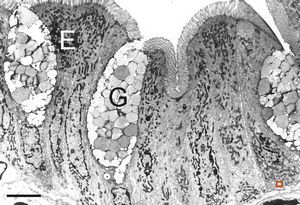

normal mucosa - duodenum - enterocytes and goblet cells